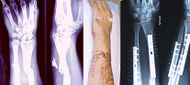

| منظر داخلي وخارجي لذراع به كسر مركب. كلا منهما قبل وبعد الجراحة. | |

- كسر مركب: وفيه تنكسر العظمة ويتمزق الجلد الذي فوقها.